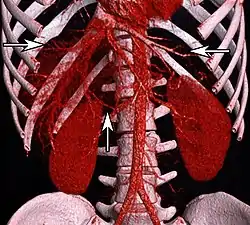

Volume rendering of an abdominal CT, with hepatic veins annotated by arrows. The aorta and branches is seen in center. | |

In human anatomy, the hepatic veins are the veins that drain venous blood from the liver into the inferior vena cava (as opposed to the hepatic portal vein which conveys blood from the gastrointestinal organs to the liver[1]: 1212 ). There are usually three large upper hepatic veins draining from the left, middle, and right parts of the liver, as well as a number (6-20) of lower hepatic veins.[2] All hepatic veins are valveless.[3]